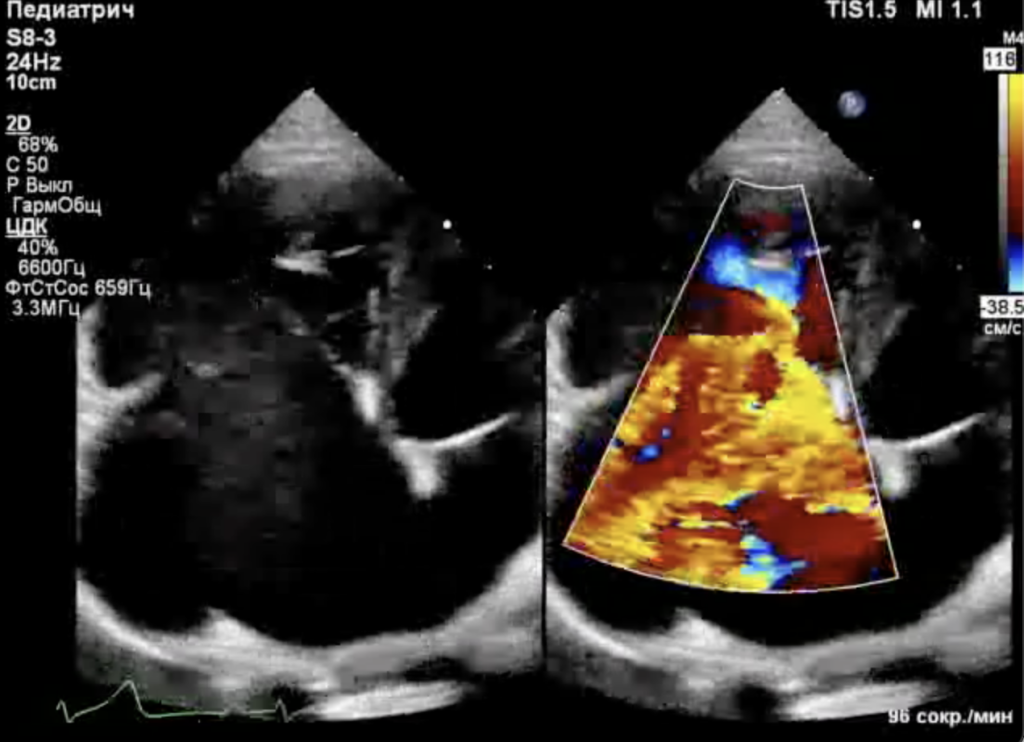

Собака находилась под наблюдением с 5-месячного возраста. При эхокардиографическом исследовании были выявлены следующие аномалии (фото 1-3):

- Выраженная дилатация правого предсердия (47 мм) и правого желудочка (конечный диастолический размер – 34 мм).

- Неделаминированная и малоподвижная септальная створка.

- Укороченные хорды.

- Выраженная регургитация (massive).

- Гепатомегалия, обусловленная застоем крови в системных венах.